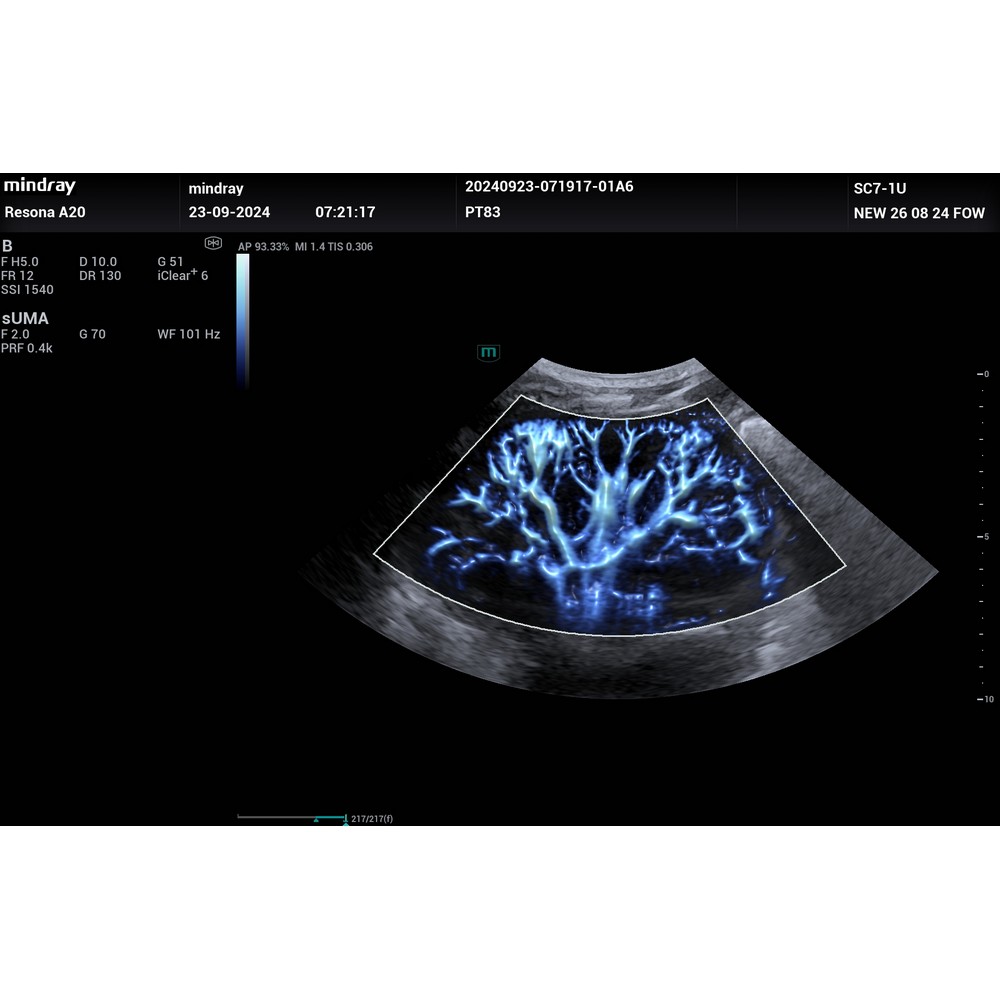

Ultra Micro Angiography (UMA) подобрява диагностичната увереност, като разширява видимостта на кръвния поток до нивото на най-малките съдове с превъзходна чувствителност и разделителна способност на кръвния поток. UMA (ултра-микроангиографията) e пробивът на традиционното доплерово изобразяване - реализира ултра-висока пространствена разделителна способност и чувствителност за изобраяване супер фин и бавен (капилярен) кръвоток.